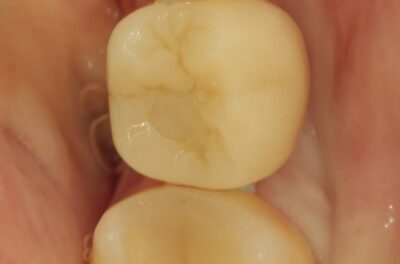

Протезирование коронками из диоксида циркония, после эндодонтического лечения — Исламов Л.А.(01.04.2026)